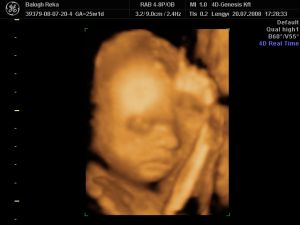

Na de a lényeg. A 4D szupi volt, megint aranyos volt a Márta. Onnan mentek egyből nyraalni, a férje kint várt rá, tök rendes volt tőle, h miattam azért bejött. Azért picit lehetett érezni, h jobban sietett, mint múltkor, meg aludt a baby, és nem ébreszgettük...de azért így is lettek nagyon jó képek. Azért gondolom nyugisabb körülmények között belefért volna egy séta, meg csokievés, ugrabugra, miegymás. De sabaj, a lelkemre kötötte, h mindenképp szóljak, h mi lett a vesémmel, mielőtt megyünk vissza, meg is akarja nézni, mondta, h mindenképp ugorjak be majd ha tudok. Hát én asszem úgy döntöttem, h jövő szerdán amúgyis el akarok menni még egy mozira is, mert szeretnék egy jókis mozgós felvételt, felébresztjük, bármi áron. :) Mert nekem már valszín nem lesz lehetőségem többet látni a kiscsajt, úh szeretnék még egy jó kis aktív mozit amúgyis. :) Talán még aug végén tudok jönni, de ez még nagyon nagyon kérdéses...

És akkor jöjjön a lényeg. :) Egyébként én tökre meglepődtem, h ennyire pufi már 25 hetesen. Én nagyon sok 4D-s képet nézegettem a neten, és 30hét és afelett szoktak már ilyen pufik lenni a babyk...na kiváncsi vagyok majd élőben... :)